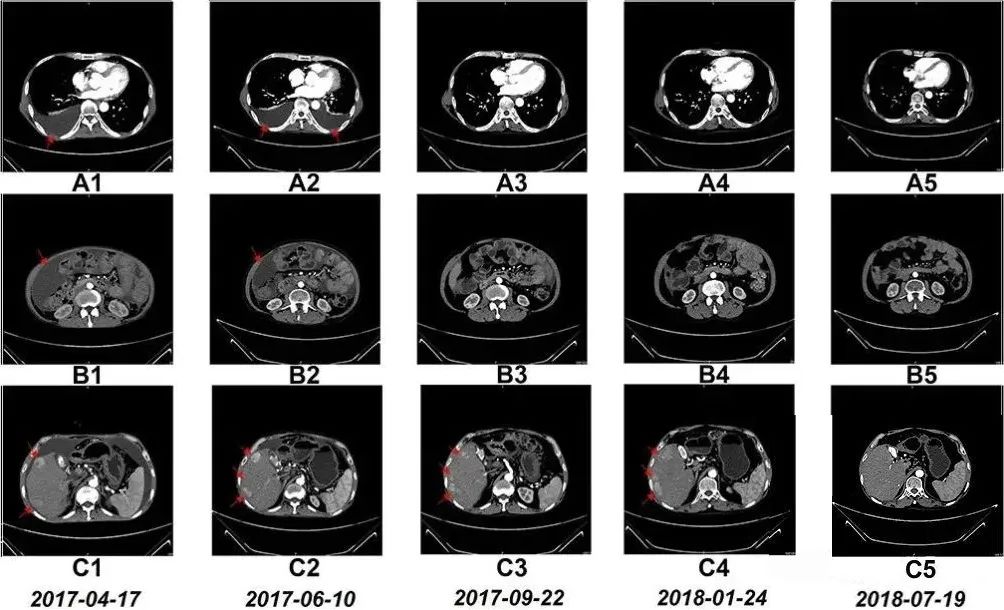

59岁的程先生连续几日右上腹出现持续性刺痛,加上就诊前有恶心、腹泻、发热等症状,提心吊胆的他在家人陪伴下来到医院检查,不查不知道,一查吓一跳,检查结果显示:胸腔积液(胸水)、腹腔积液(腹水)、肝右叶有多个肿瘤,程先生最后被确诊为弥漫性肝癌晚期(IV期)。

随后的8个月里,患者接受了一系列的手术、化疗和药物治疗。2017年3月,他开始尝试NK细胞输注治疗,值得一提的是,患者在NK细胞治疗期间,除营养支持、心理干预等辅助疗法之外,未接受其他治疗。

令患者本人和医疗团队都格外惊喜的是,7个月后,患者的胸水和腹水明显减少,治疗17个月后,CT扫描显示他肝右叶的多个肿瘤显著缩小。淋巴细胞亚群出现的变化表明免疫功能得到改善。此外,患者的肝功能水平和白细胞、血小板、中性粒细胞和淋巴细胞计数也保持在参考范围内。

更难得的是,据研究小组跟踪获悉,截至发稿,患者目前仍带瘤生存。

上文提到的晚期肝癌患者程先生,正是通过15个月的NK细胞输注,使体内NK细胞比例提升近7倍,同时CD8+T细胞等关键免疫指标显著改善。影像学检查显示其胸腹水消退,肝部肿瘤缩小,生存期远超预期。